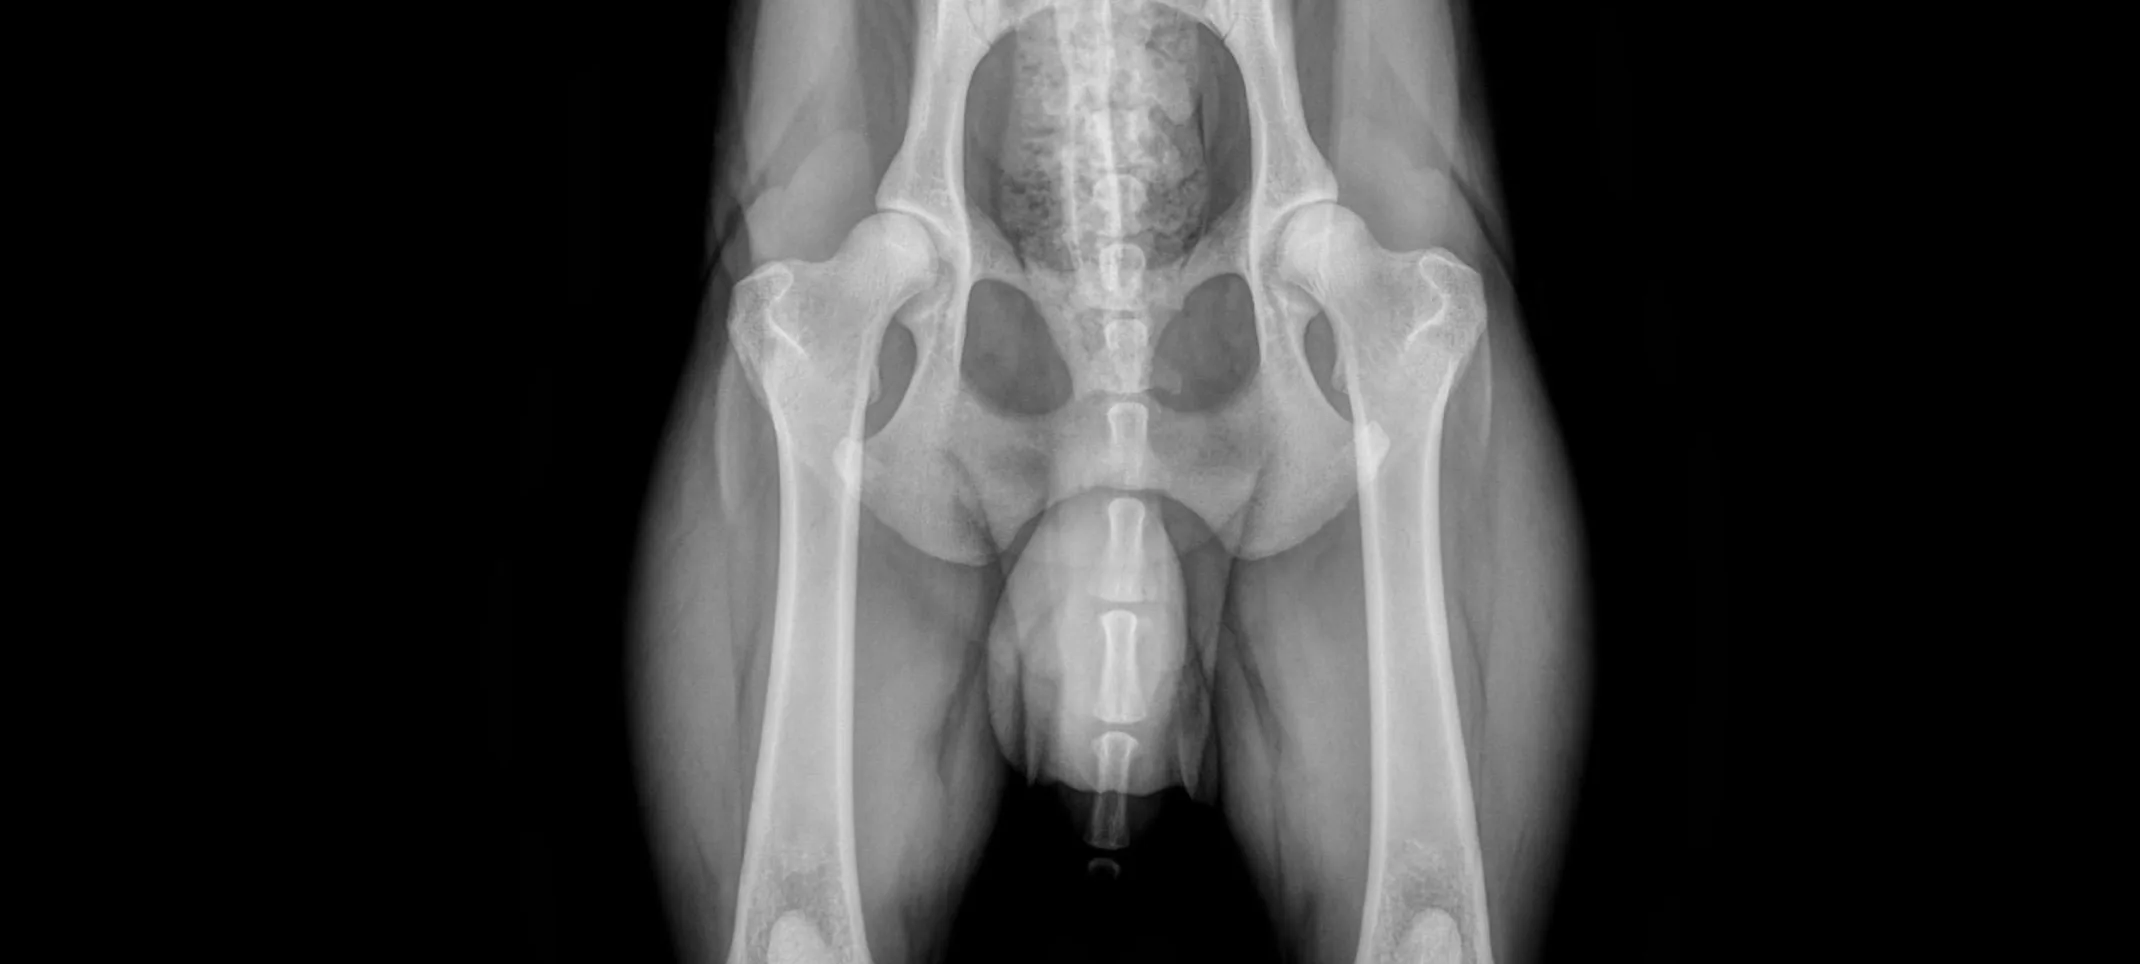

The PennHIP method consists of three separate radiographs: the distraction view, the compression view, and the hip-extended view. The distraction view and the compression view provide precise measurements of hip joint laxity and congruity, respectively, while the hip-extended view gathers supplementary information about the existence of OA in the hip joint.